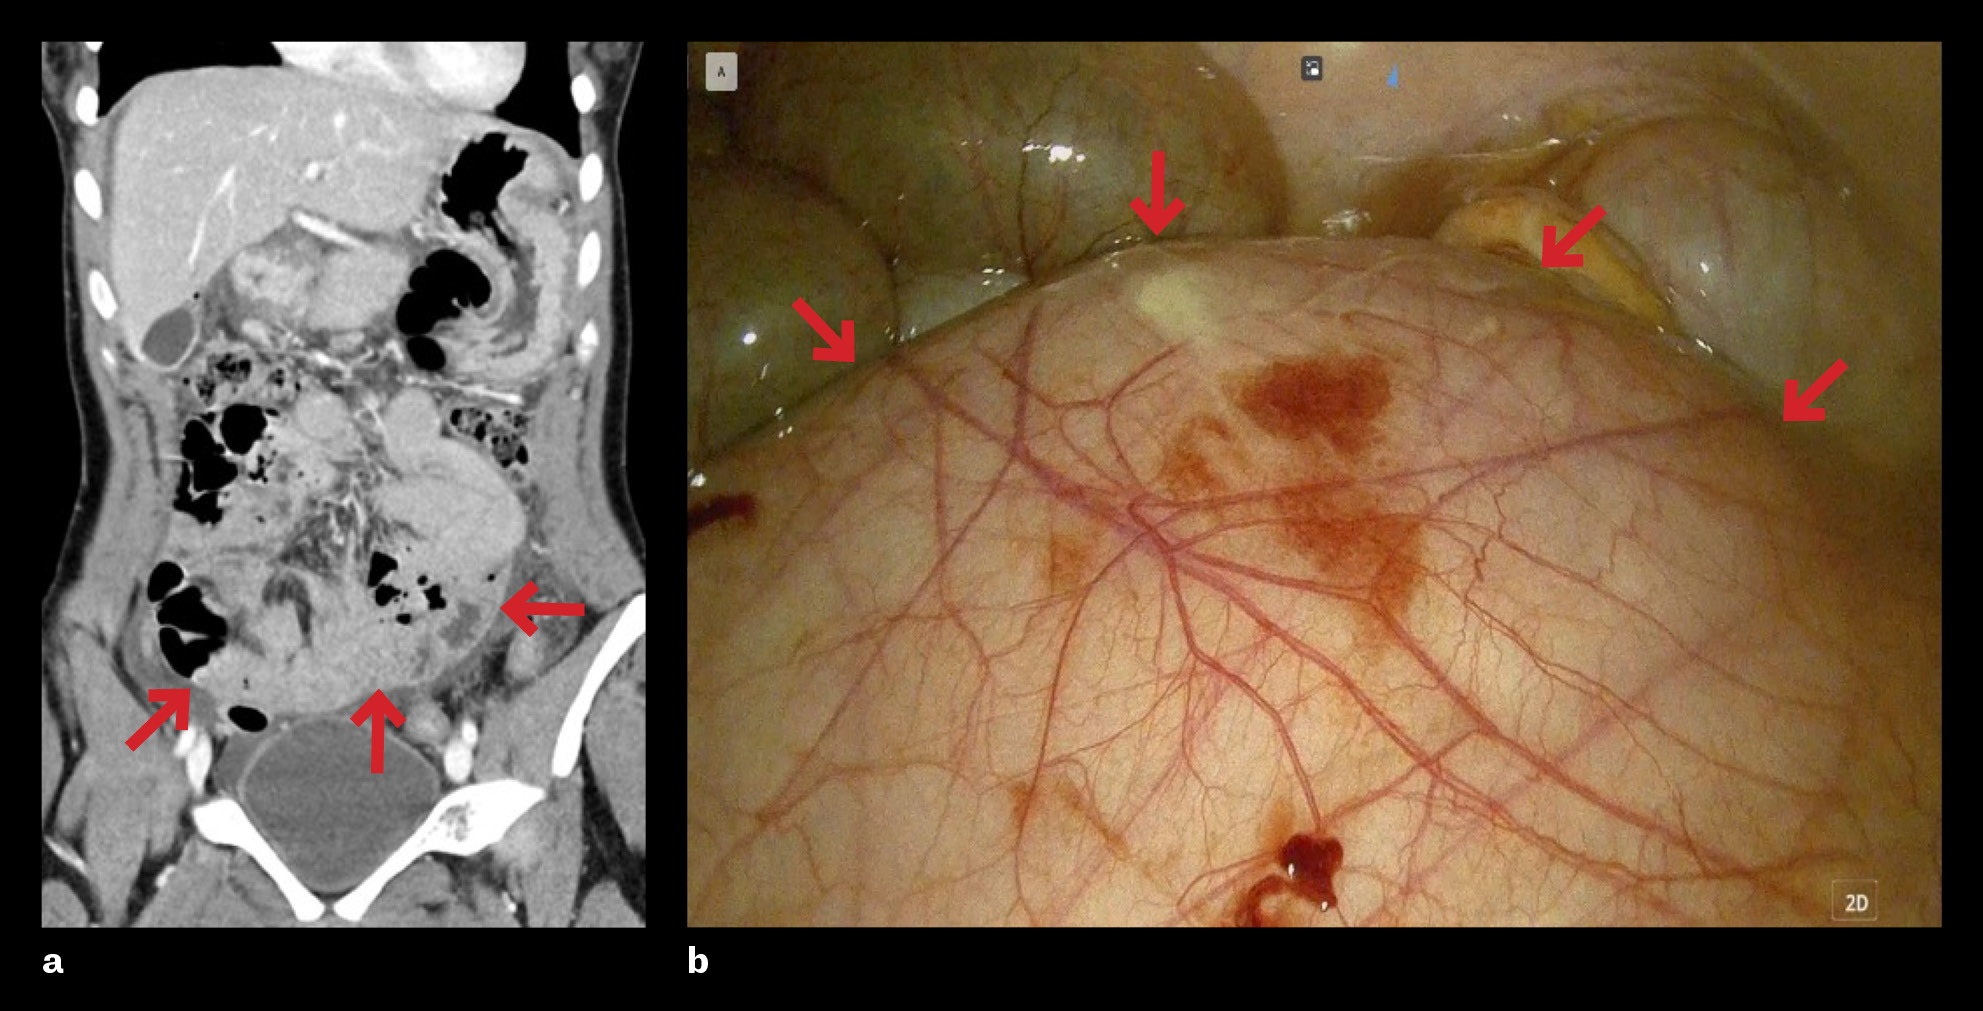

Bildene viser medfødt peritoneal innkapsling som ble avdekket tilfeldig hos en ung kvinne operert for perforert ulcus duodeni. Hun ble innlagt ved gastrokirurgisk avdeling med epigastriesmerter av ett døgns varighet, med kraftig forverring samme morgen som innleggelsen. CT abdomen viste fri luft i bukhulen og mistenkt veggdefekt i bulbus duodeni. Tilstanden var forenlig med perforert ulcus duodeni, og hun ble laparoskopert to timer etter innkomst. Hullet ble sydd og tildekket med en flik av oment (tegmentert). Under operasjonen så man påfallende lite tynntarm, og en stor peritonealkledd oppfylning på bakre bukvegg.

På grunn av de uventede peroperative funnene ble CT-bildene og operasjonsvideoen gjennomgått i etterkant. Funnene er mest forenlig med medfødt peritoneal innkapsling, en sjelden tilstand hvor en tynn, aksessorisk peritonealmembran dekker hele eller deler av tynntarmen. Peritonealmembranen er festet lateralt til colon ascendens og descendens, superiort til colon transversum og inferiort til bakre overflate av parietale peritoneum. De fleste tilfeller er asymptomatiske og avdekkes tilfeldig peroperativt eller ved obduksjon (1). For pasienter som utviser symptomer, er magesmerter, kvalme og oppkast vanligst, ofte som uttrykk for partiell eller komplett tynntarmsileus.